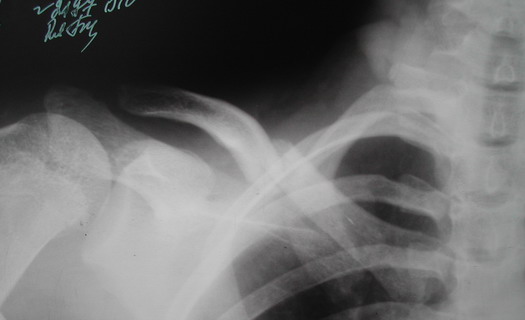

Во время стажировки в Австрии не мог не поинтересоавться, как австрийские хирурги лечат переломы ключицы. Оказалось, при переломах без смещения или с небольшим смещением накладывают восьмиобразную повязку, в остальных случаях выполняют остеосинтез пластинами.